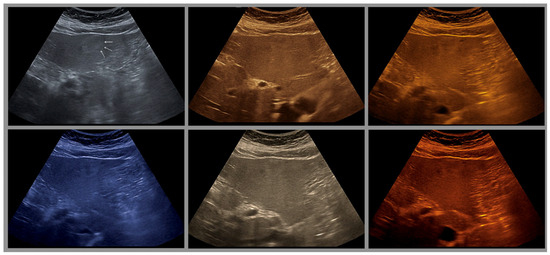

Is There an Ideal Color Map?

| Color | Advantages |

|---|---|

| Sepia (Yellow-Brown) | Mimics familiar tones from black-and-white photography |

| Enhances contrast while preserving anatomical detail | |

| Offers intuitive brightness mapping (lighter tones = more echogenic areas) | |

| Preferred by students and experts alike | |

| Blue | Provides excellent depth perception |

| Reduces visual fatigue by avoiding glare and high saturation | |

| Often favored by experienced examiners for high-resolution detail | |

| Facilitates alertness and performance on tasks requiring sustained attention | |

| Green (muted tones) | Offers a balanced hue that avoids excessive saturation |

| Enhances intermediate echogenicity levels without causing artifacts | |

| Especially helpful for liver and parenchymal tissue imaging |